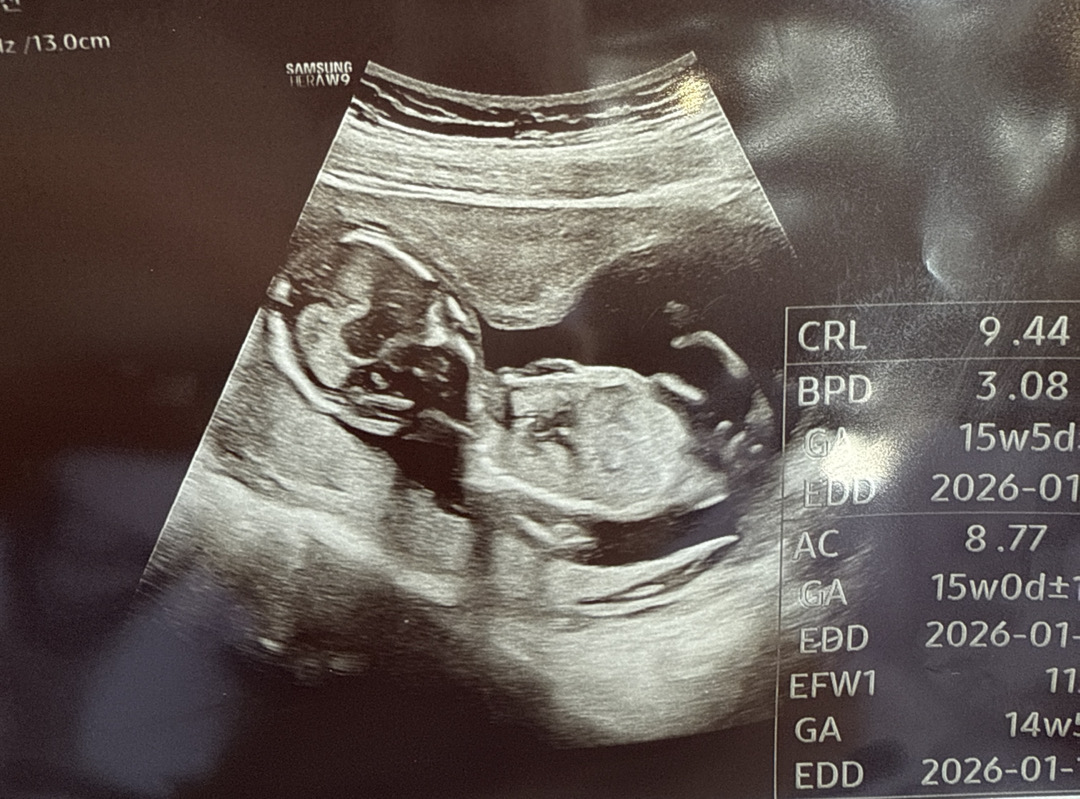

14주차 이거 탯줄인가요? 남자인가요 딸인가요

밑부분이 성기부분같이 보이는데 탯줄인가요? 전 왜 🌶️로 보이죠